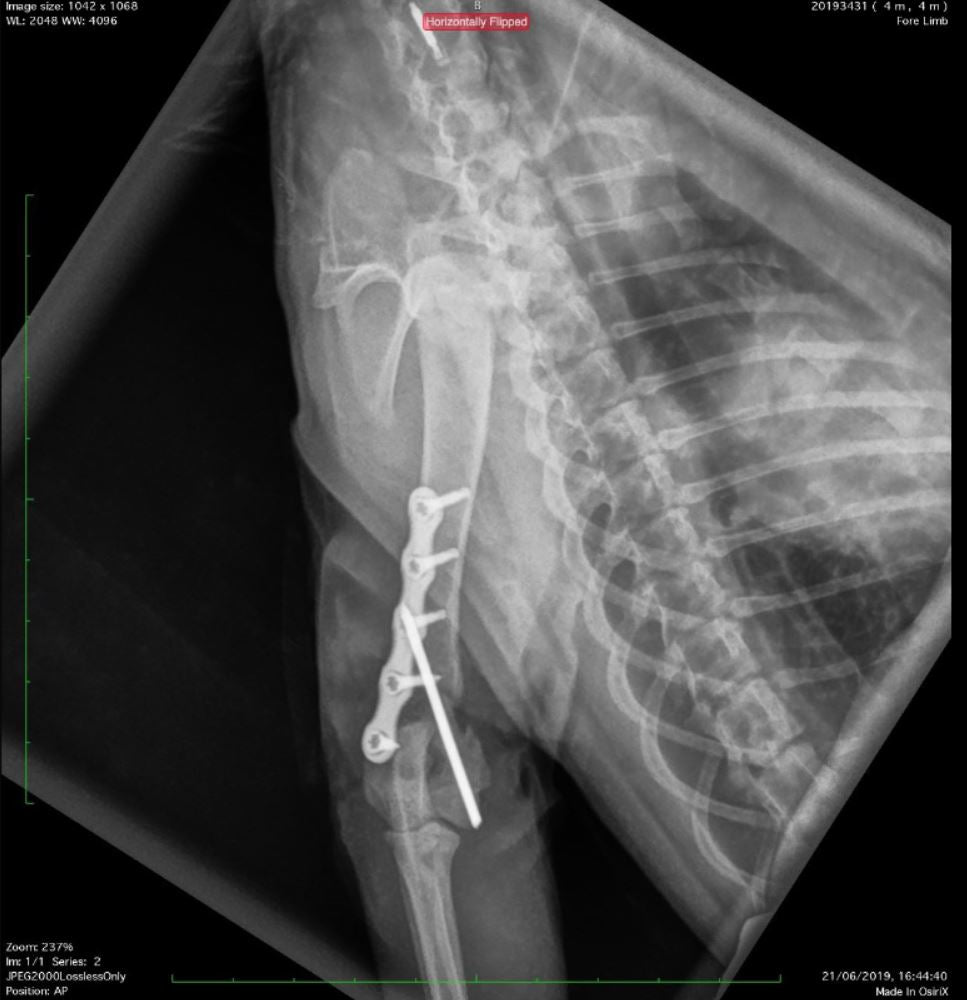

This course is designed for small animal practitioners seeking practical, effective methods to manage long bone fractures in dogs and cats. Participants will learn simplified techniques suitable for both straightforward and comminuted fractures, using modern implants that enhance surgical efficiency and reduce costs. By following key principles of fracture repair, complications can be minimized and outcomes improved.

Through a combination of lectures, clinical case discussions, and hands-on practice, attendees will gain confidence in choosing appropriate fixation methods and performing repairs. Practical sessions include fracture repair on plastic bone models and cadavers, followed by postoperative radiographs to assess technique and reinforce learning.

Apply the biomechanics of intramedullary pins, cerclage wires, bone screws, and plates, including compression, neutralization, and bridging methods